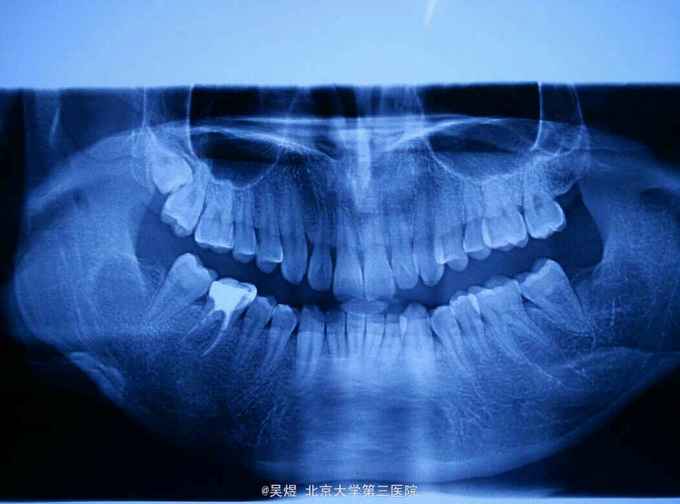

18埋伏,表面牙龈未见异常。曲断示:18高位水平阻生,牙冠与17及上颌窦关系密切。

术后一周拆线,伤口愈合良好,无不适。 讨论:上颌埋伏阻生智齿由于操作空间及视野狭窄一般拔除难度相对稍大。但相对于下颌骨上颌智齿周围骨质较疏松。除外高位,水平,牙冠与邻牙紧密接触的类型外,大部分近中阻生的都不需要分牙,一般稍去骨增隙挺松就可拔除。此外,由于上方有上颌窦的存在,特别需注意增隙的力度,术前也应和患者详细交待上颌窦瘘的风险及后续处理。